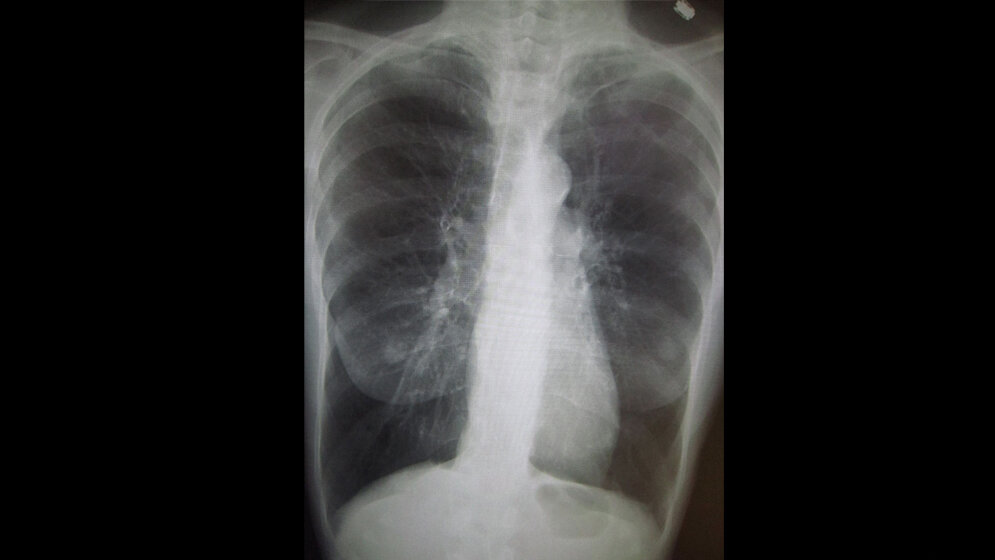

Bei Erkrankten verengen sich die Atemwege, Lungengewebe wird zerstört. Vermehrt wird Schleim in den Bronchien produziert, Betroffene müssen stark husten und haben Auswurf. Die Lunge erleidet einen Strukturverlust. Statt vieler kleiner Lungenbläschen gibt es größere Blasen. So geht die für den Gastaustausch notwendige Oberfläche verloren. Betroffene merken es zuerst bei Belastungen wie Treppen steigen oder Rad fahren. „Unsere Lunge besitzt zwar große Reserven. Ihre Kapazität reicht von still sitzen bis zum Marathonlauf“, erläutert der UKL-Pneumologe, „doch wenn durch die Krankheit überschüssige Kapazitäten verlorengehen, führt das schon bei leichten Tätigkeiten zu Luftknappheit.“ Das Problem: „Was an Struktur der Lunge verloren ist, ist weg. COPD ist nicht heilbar, sondern fortschreitend. Man kann nur versuchen, den Verlust zu bremsen“, betont Prof. Wirtz.

Weil auch die Elastizität des Organs verlorengegangen ist, sind die Atemwege verengt. So bleibt beim Ausatmen viel Luft im Thorax, also im Brustkorb gefangen, zu wenig neue Luft kann eingeatmet werden. Bei Belastungen verschärft sich dieser Zustand noch. Medikamente können hier zumindest helfen, die Verkrampfungen zu lösen und für eine bessere Entleerung der Lunge zu sorgen.